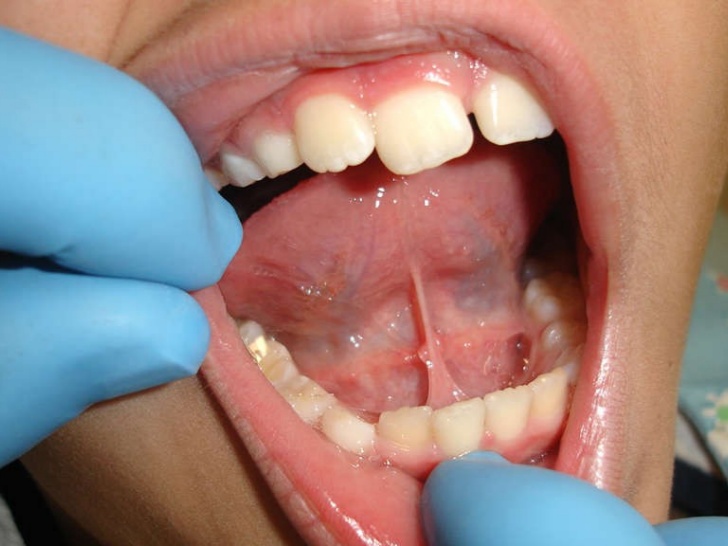

El frenillo es un pliegue vertical de mucosa que une la parte delantera de la lengua al suelo de la boca. Se dice que cuando el frenillo lingual es más corto de lo normal tiende a limitar los movimientos de la lengua y no se puede tocar el paladar o el labio superior.

El frenillo como pequeñas bandas de tejido fibroso muscular y en ocasiones mixto que son recubiertos con una membrana mucosa, algunas veces generan problemas por el tamaño.

La anquiloglosia lingual es el desarrollo deficiente del frenillo es decir que este es más corto de lo normal.